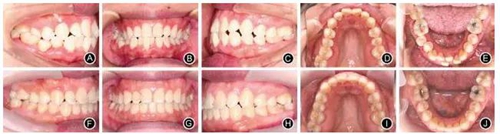

例1:患者女,29歲,主訴要求排齊上下牙列。臨床檢查,雙側(cè)磨牙輕度近中關(guān)系,下牙列中度擁擠,前牙對(duì)牙合,右側(cè)后牙反牙合,前牙Bolton比為81.86%。正畸設(shè)計(jì)減數(shù)右下中切牙,維持后牙近中關(guān)系。全口固定矯治,上頜牙弓擴(kuò)大,下頜拔牙間隙用于排齊牙列和適度內(nèi)收下前牙。固定矯治19個(gè)月,下頜舌側(cè)固定保持,2年后改為Hawley保持器保持(圖2)。

圖2典型病例1

A.治療前右側(cè)位牙合像 B.治療前正位牙合像

C.治療前左側(cè)位牙合像 D.治療前上頜口內(nèi)像

E.治療前下頜口內(nèi)像 F.治療后右側(cè)位牙合像

G.治療后正位牙合像 H.治療后左側(cè)位牙合像

I.治療后上頜口內(nèi)像 J.治療后下頜口內(nèi)像